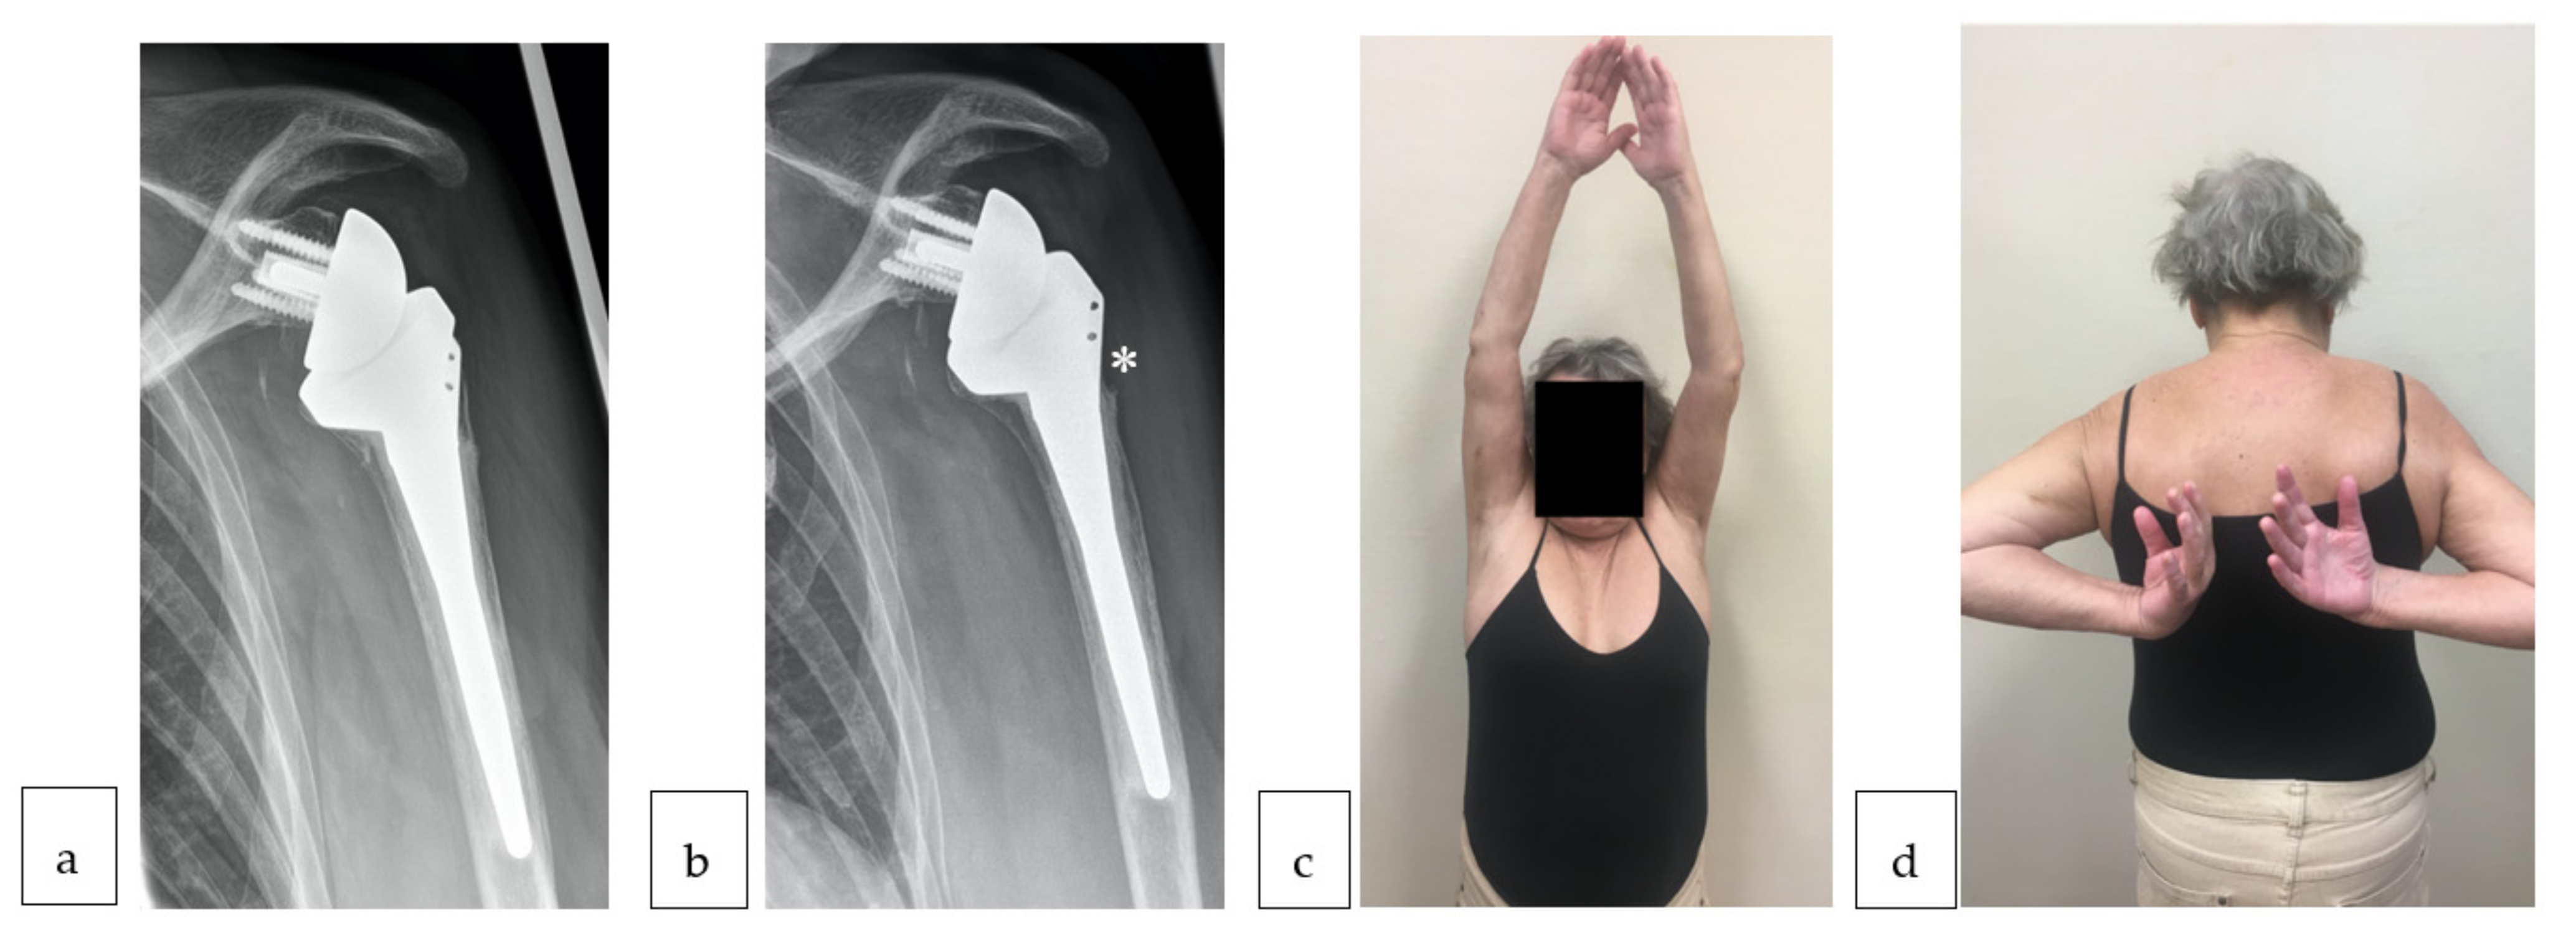

2.2. Surgical Technique and Rehabilitation Protocol

3.3. Clinical Impact of Tuberosity Healing and ERLS

3.4. Complication